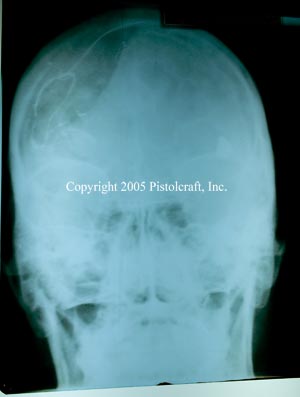

.380 Wound X-Rays

These x-rays are of a patient who received a contact wound from a .380 caliber firearm.

Note that this patient is still alive, and functions with a deficiency of about 30%.

The deformation of the brain is significant, and the bullet clearly visible in the picture.